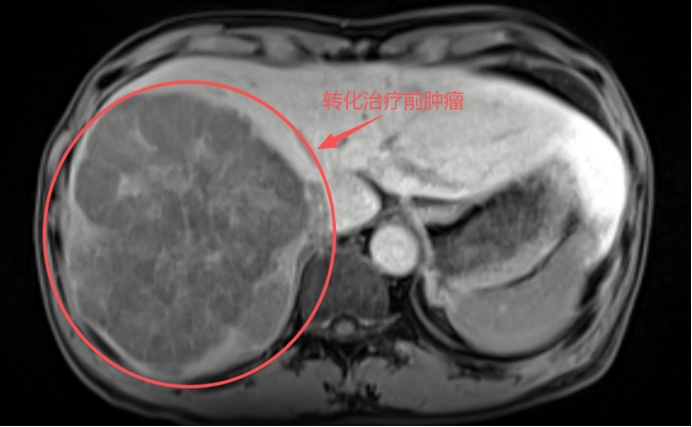

肿瘤显著缩小:肝右叶巨大肿瘤明显缩小,从173mm×124mm×142mm缩小到108mm×90mm×84mm,活性明显降低。

转化治疗前肿瘤左半肝体积占比70%左右